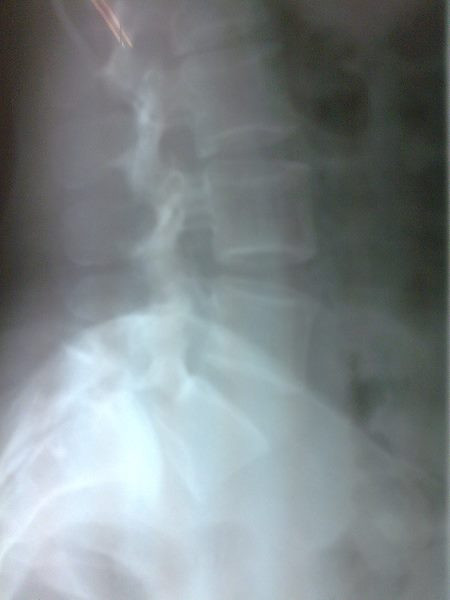

Radiografías con enfoque en fisiatría

Envíado por Dr. Hernán Darío Sánchez Ramos